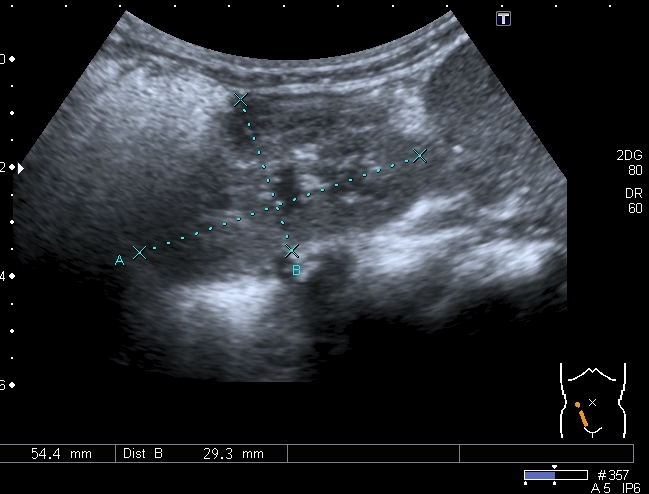

Увеличены парааортальные лимфатические узлы.